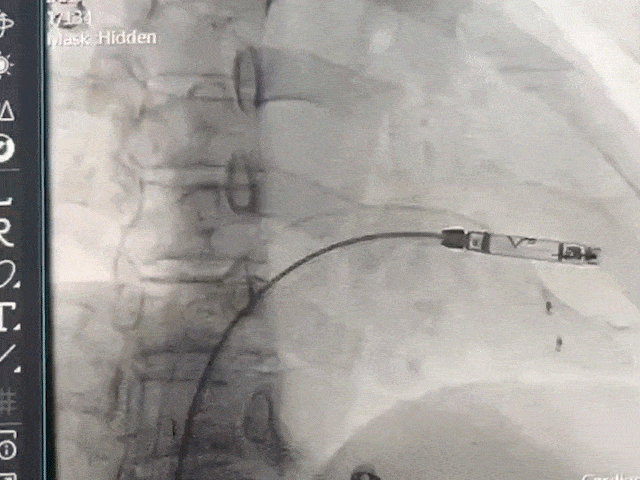

手术过程部分展示

后撤保护套筒并释放调弯,保持合适张力,避免前向压力

开始旋入AveirVR

1.5圈时立即进入对接栓模式,并做调弯测试

左前调整同轴

释放无导线起搏器